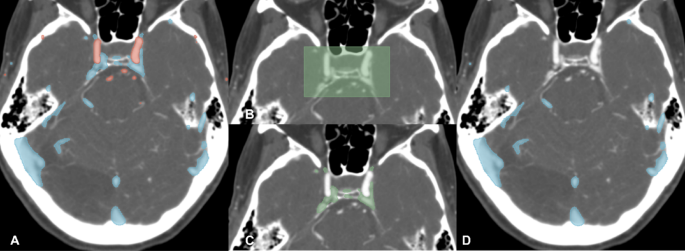

The artery and vein masks were produced from each inference (test) CTA using our publicly available intracranial artery-vein segmentation algorithm (reported separately)2,13,17. This algorithm was trained using a nnUNet model on 4D dynamic CTA data, with cerebral veins and arteries annotated via a semi-automatic MRA-based annotation tool13 (Fig. 2A). Since CVS, an anatomically unique venous structure located at the base of the brain, overlaps spatially with a number of common arterial aneurysm locations, we produced the CVS mask in a fully automated manner using the outputs of the vascular segmentation model, as described below, and subtracted it from the vein mask.

Arterial (red) and venous (blue) segmentation masks of intra and extracranial structures (A). The cavernous venous sinus (CVS) region box derived from an atlas, registered to the same CTA using the ANT registration framework (B). The CVS mask defined by overlap between the CVS region box and the venous mask (C). Vein mask with CVS mask subtracted (D).

Cavernous venous sinus mask

The patient-specific CVS segmentations were produced within the pipeline from each inference (test) CTA. To localize the CVS region, a bounding box derived from our CTA vascular atlas13 was aligned to each inference CTA image using affine registration via the Advanced Normalize Tool (ANT) framework. This box was then expanded by 3.2 mm (8 pixels) in 3 dimensions to ensure inclusion of all surrounding anatomical structures (Fig. 2B). The final CVS mask was produced by considering only voxels contained in both this expanded CVS region box and the venous segmentation mask (Fig. 2C and D).